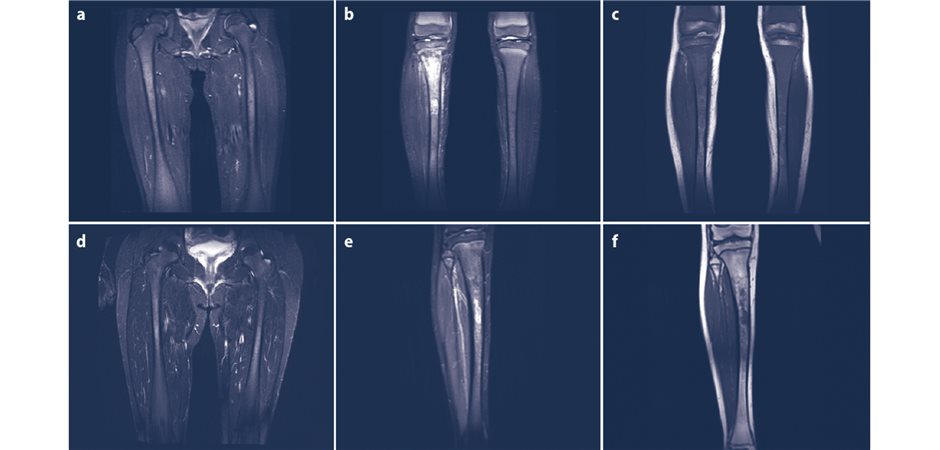

Die ersten Symptome manifestieren sich bei den meisten Betroffenen bei der Geburt oder im frühen Kindesalter. CEP zeichnet sich durch Photosensitivität lichtausgesetzter Hautarealen aus; dies kann eine größere Fragilität, die Entwicklung von Blasen oder gar zur Photomutilation führen (stark entstellende Photodermatose). Letzteres ist durch eine Anhäufung des Häm-Vorläuferstoffs Uroporphyrinogen I in der Haut, Knochen und anderem Gewebe verschuldet. Hypertrichose, fokale Hyper/Hypopigmentation und Hautverdickung können auftreten. Die Ausprägung der Symptome eines Betroffenen kann variieren.